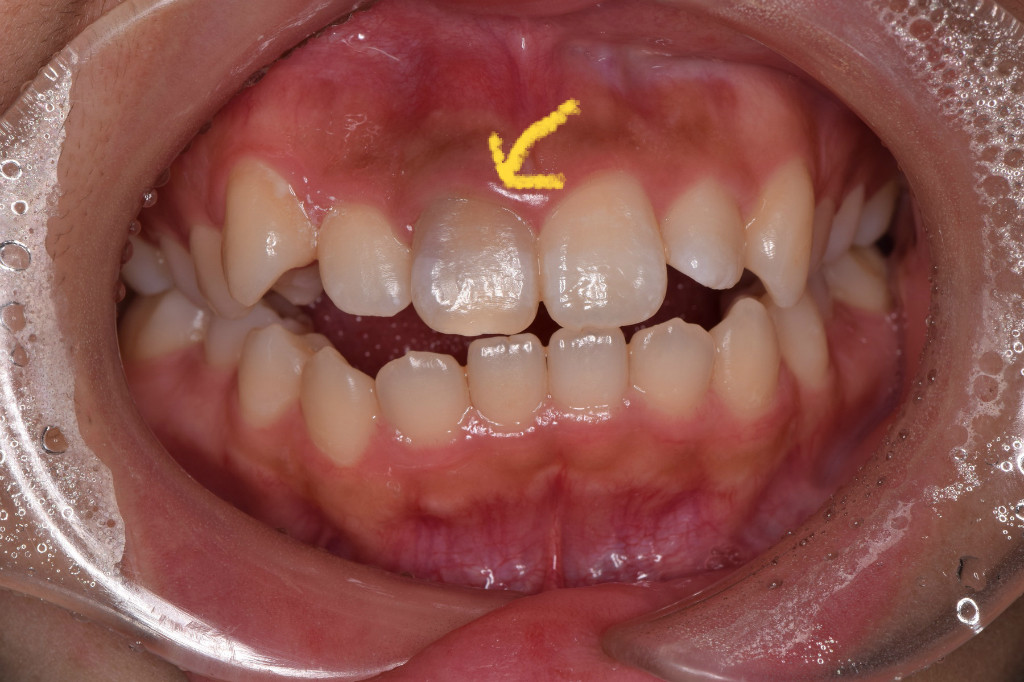

神経がない歯は徐々に歯の色が変わっていき、グレーっぽくなってしまいます。

そこで、歯の裏から漂白する薬剤をいれること、1週間後。

こんなに綺麗に白くなりました。